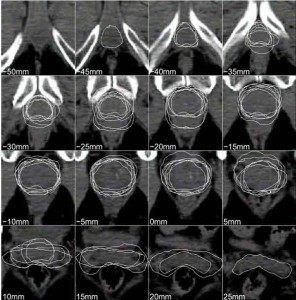

RADIOTERAPIA INTRAOPERATORIA – Una sferetta che spara raggi X direttamente nell’area della lesione, durante l’asportazione del carcinoma mammario, potrebbe rivoluzionare nel giro di pochi anni la cura, eliminando – in casi selezionati – la necessità di sottoporsi alle tradizionali tre-sei settimane di radioterapia postoperatoria effettuate per uccidere le eventuali cellule malate rimaste ed evitare la formazione di recidive. Lo sostiene il primo studio internazionale che ha confrontato la radioterapia intraoperatoria mirata (TARGIT) con quella convenzionale esterna. Condotto da Jayant Vaidya della University College London, il test era stato avviato nel 2000 e negli anni ha raccolto oltre 2.200 adesioni da 28 centri di nove Paesi diversi (tra cui l’Italia che ha partecipato dal 2004 con il Centro di Riferimento Oncologico di Aviano e l’Ospedale San Giuseppe di Empoli). «Dopo la chirurgia conservativa, circa il 90 per cento delle recidive locali si ripresenta all’interno dello stesso quadrante – spiegano gli autori -. Per questo concentrare la dose radioterapia al “letto tumorale” durante l’operazione potrebbe essere un’opzione utile per un determinato gruppo di pazienti». Secondo quanto riferito dai ricercatori responsabili per le sperimentazioni avvenute al centro di Aviano, Samuele Massarut, chirurgo senologo, e Mario Roncadin, radioterapista, «il trial ha dimostrato che sul campione di donne arruolate, di età maggiore di 45 anni e con tumori non invasivi definibili a rischio medio basso di recidiva, la radioterapia intraoperatoria è efficace quanto quella convenzionale». I vantaggi di un’unica seduta intraoperatoria per le malate sono evidenti: meno stress e minori spostamenti, ma anche inferiori effetti collaterali perché i raggi così “raccolti” evitano di colpire gli organi limitrofi, come cuore, polmone ed esofago. Con un dose concentrata e localizzata, poi, la tossicità risulta minore come l’impatto estetico. Anche il Servizio sanitario nazionale ci guadagnerebbe, perché si riducono i costi e le liste d’attesa in radioterapia si accorciano.